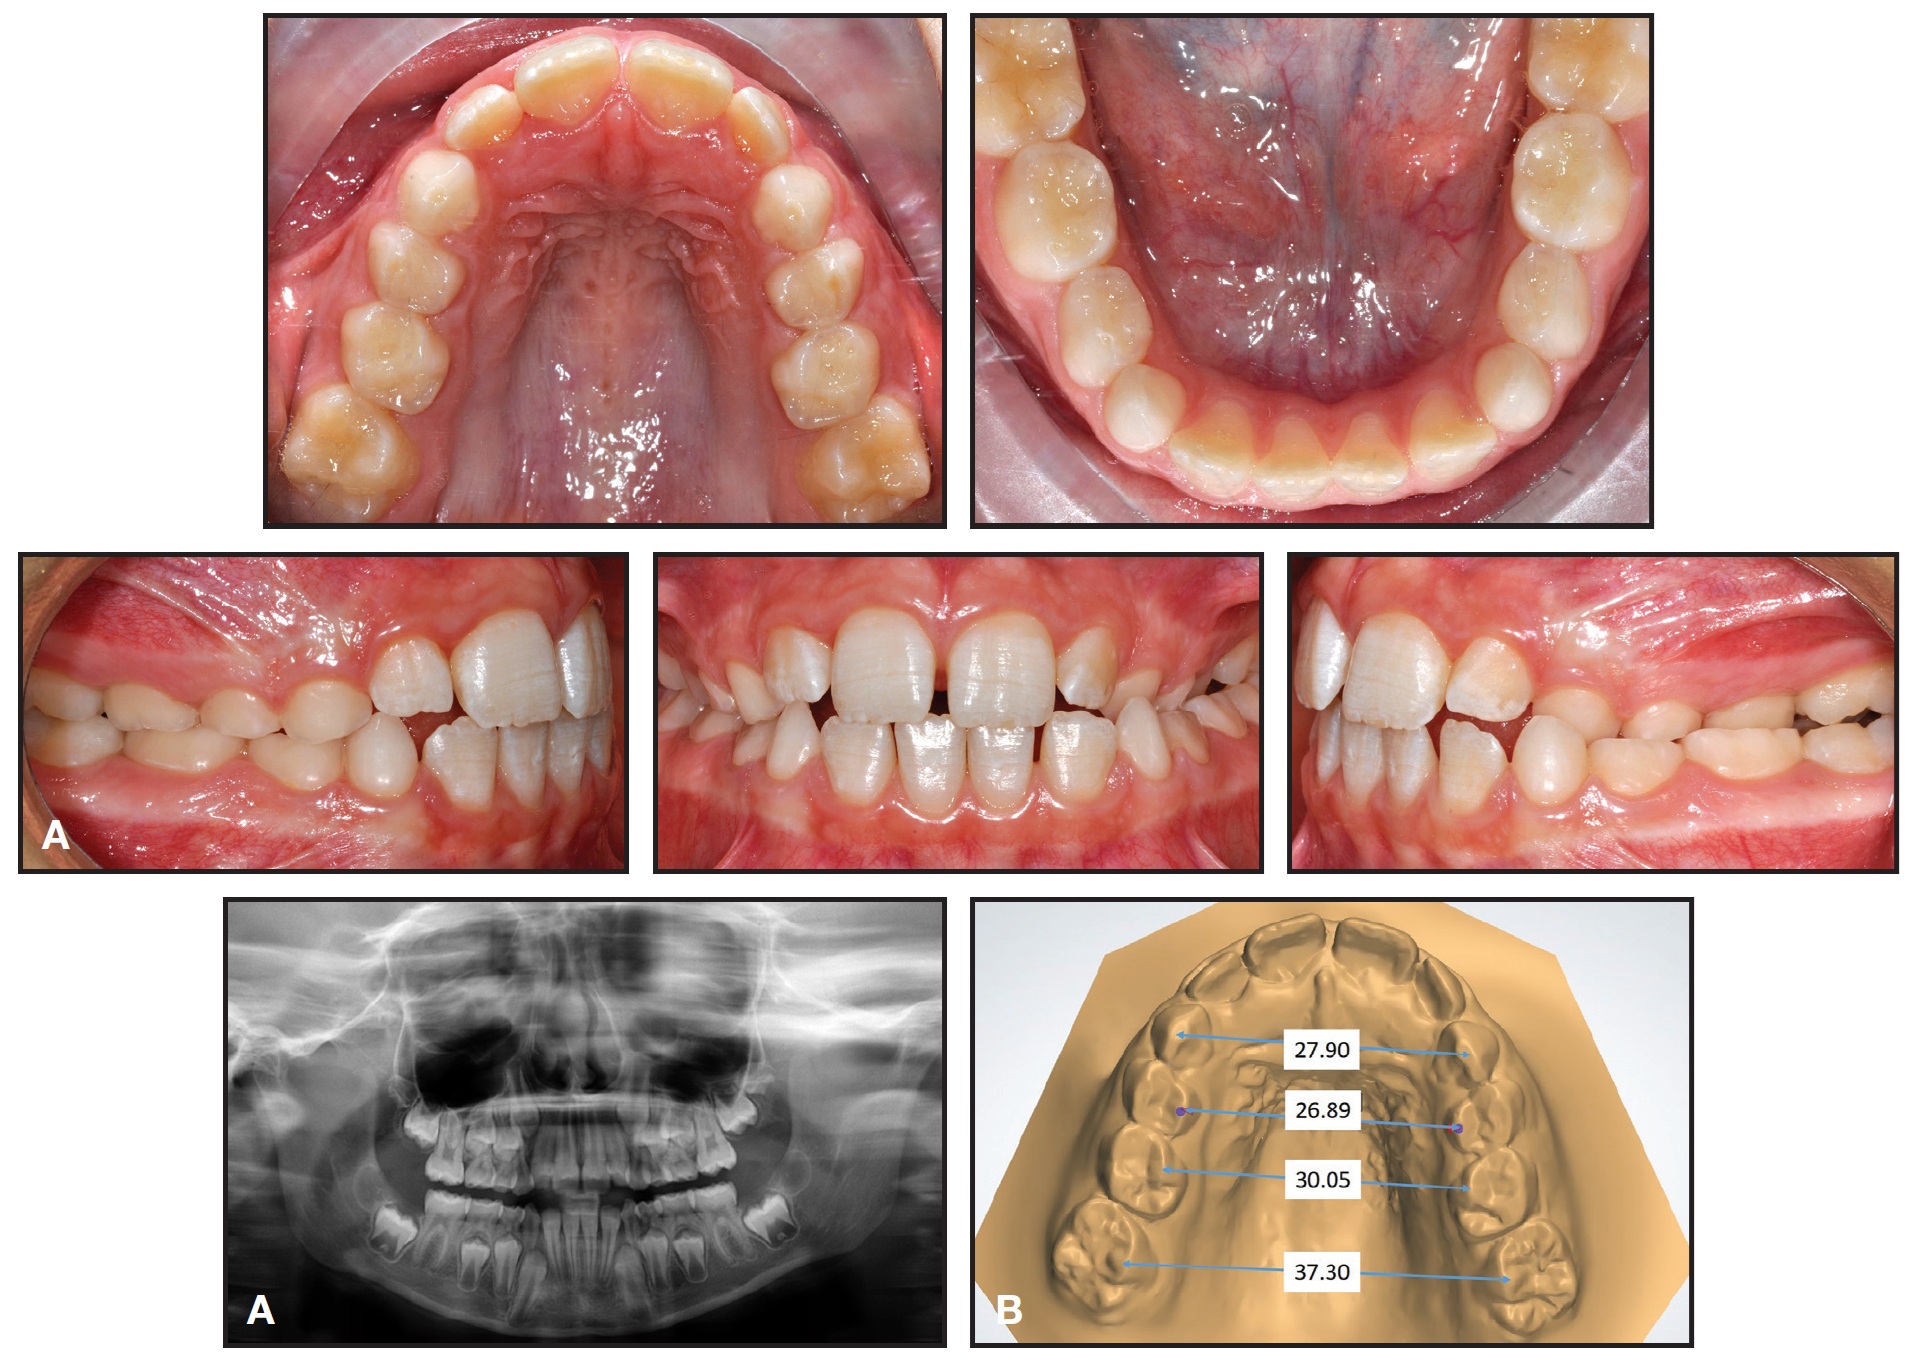

After another three months of retention, the appliance was removed. Final records confirmed that the crossbite and midline deviation were corrected; the maxilla was expanded enough for eruption of the upper lateral incisors; and the first permanent molars had spontaneously expanded and rotated (Fig. 10, Table 2). Treatment results were stable nine months later (Fig. 11).

Fig. 10 Case 2. A. After three months of retention (images obtained from intraoral scan). B. Superimposition of pre- and post-treatment results on palatal rugae.

Fig. 11 Case 2. Patient nine months after treatment.